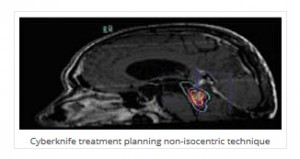

Η καθιερωμένη θεραπεία συνιστάται στην μέγιστη χειρουργική εξαίρεση, την ακτινοθεραπεία και την χημειοθεραπεία.